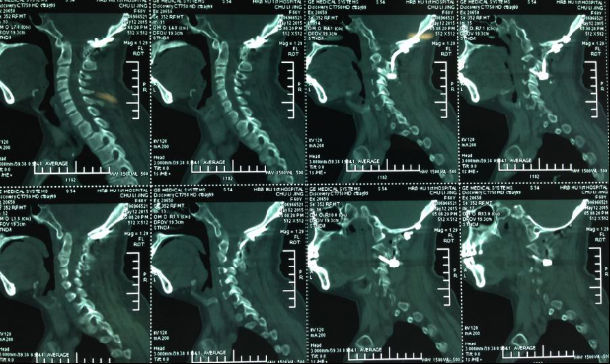

3影像学检查

手术前前屈位X光片寰枢椎脱位(寰齿前间隙7mm)。寰枢椎三维CT见寰枕融合,颅底陷入(齿状突位于钱氏线上14.2mm),右侧枢椎椎弓根发育狭小(小于2mm),磁共振显示小脑扁桃体下疝、颈髓损伤伴椎管狭窄。

4术前片子